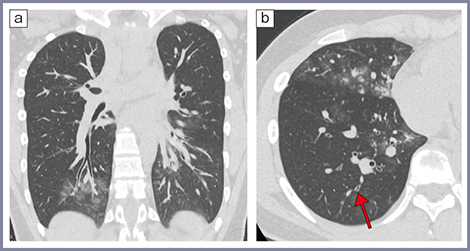

COVID-19肺炎では病変部分の血管拡張が見られることも重要な所見である(図3)。正常な肺では局所の換気が低下すると末梢の肺動脈が収縮し,換気低下部位の肺動脈血流も低下する。これをhypoxic vasoconstrictionと呼ぶ。しかし,COVID-19肺炎ではこの機能が障害され,病変部分に多量の血液が流れる結果,低酸素血症を助長すると考えられている。われわれは,高精細CTでCOVID-19肺炎の症例の血管径を測定し,酸素投与を必要とするような肺炎では血管が太いことを報告した4)。

ところで,第7波で見られたオミクロン株では,パンデミック初期に見られた末梢優位,非区域性の斑状病変とは画像パターンが異なり,区域性に病変が広がり,気管支壁肥厚も目立つことが報告されている5),6)。図4は第7波(2022年7月)の症例だが,気管支血管束に沿った淡いすりガラス影(a)や,気管支壁肥厚(b)が見られる。本症例は,10歳代,男性で,CT撮影は120kV,60mA,1.3mSvの低線量で撮影している。当施設では,被ばく低減を考慮し,特に若年者では積極的に,低線量CTを施行している。Aquilion Precisionでは画像再構成技術を含め,低線量でも精度の高い画像が得られている。

図3 30歳代,女性,中等症ⅡのCOVID-19肺炎(2020年の症例)4)

a:高精細CT軸位断像 b:病変部分の斜位断拡大像

図4 10歳代,男性,中等症ⅡのCOVID-19肺炎 (2022年の症例)